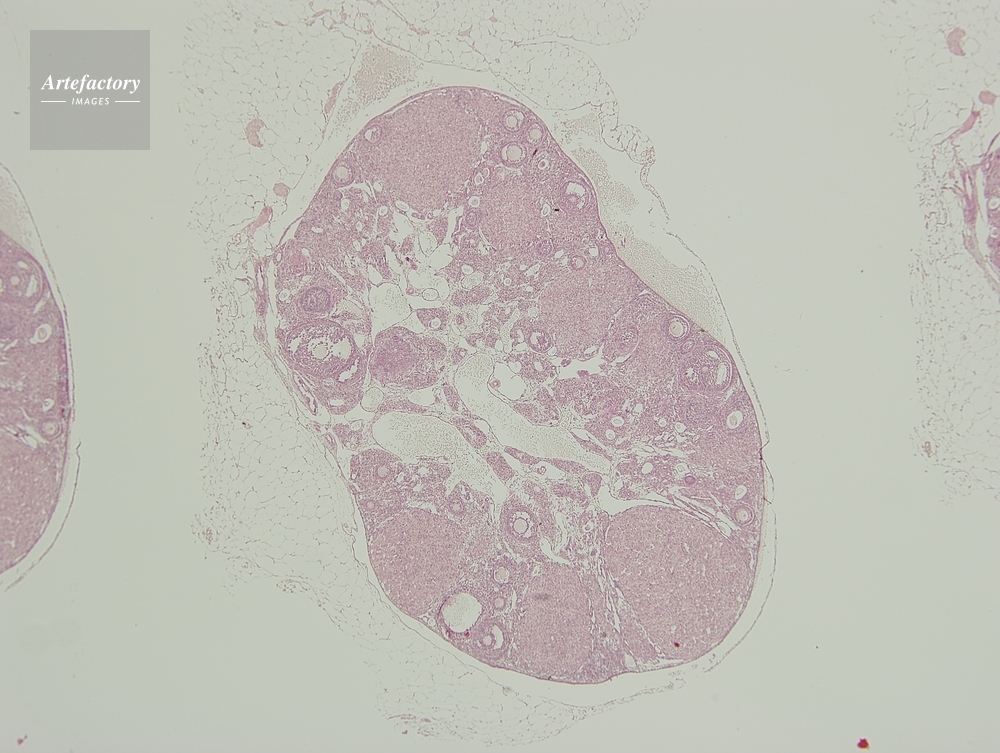

| 作品タイトル | マウス,卵巣 | モデルリリース | なし | |

| 作家 | OLYMPUS CORPORATION Technolab | プロパティリリース | なし | |